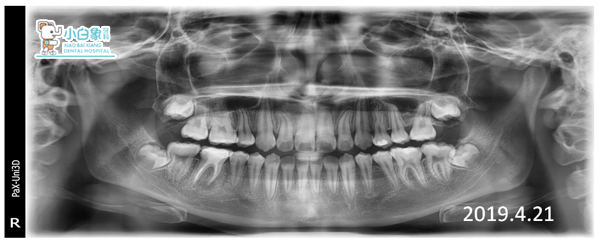

治疗结束X线片